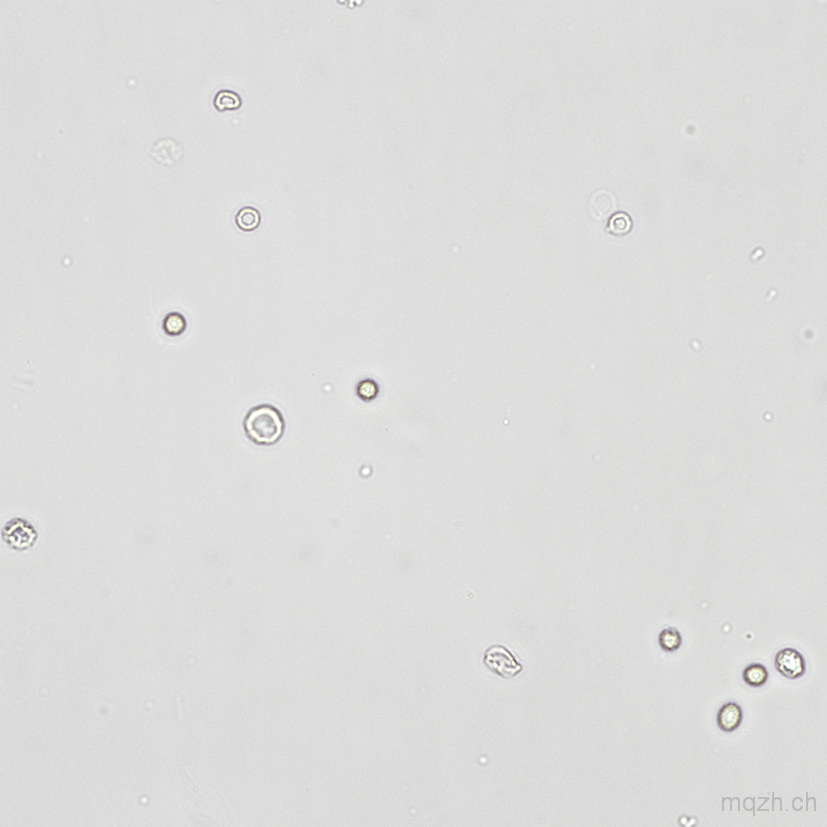

MQ 2025-4 Urinary Sediment U4